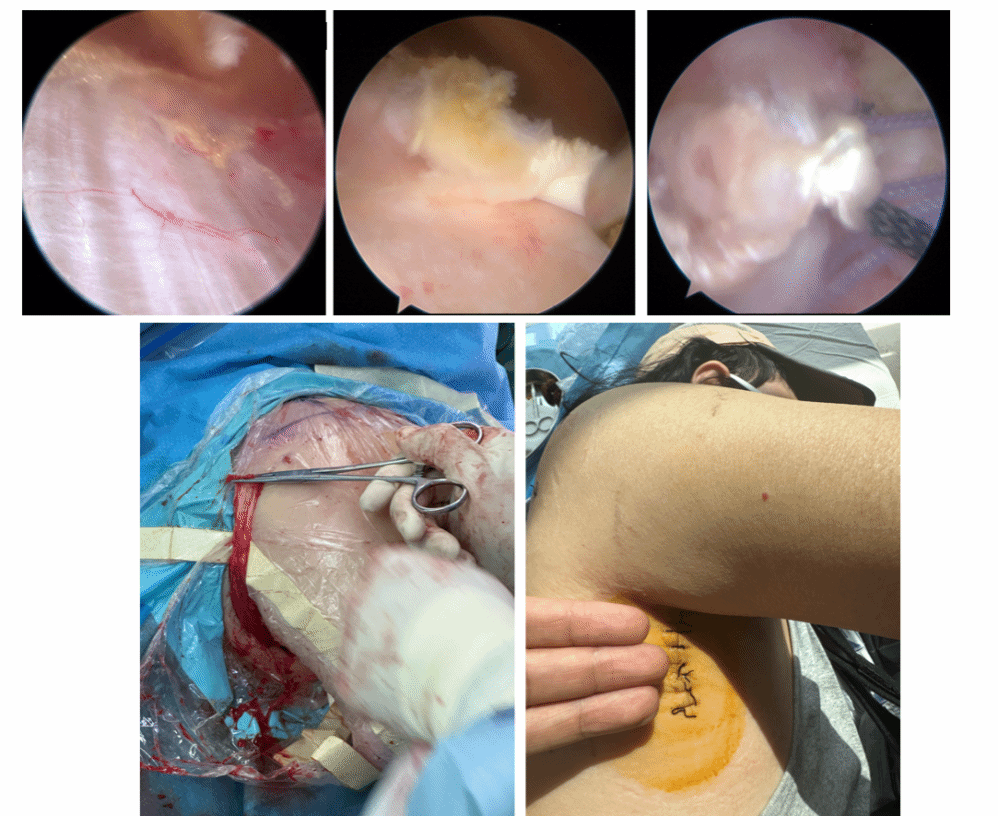

关节镜辅助背阔肌转位治疗不可修复后上型肩袖撕裂

全镜下胸小肌腱带骨块转位治疗不可修复肩胛下肌健撕裂